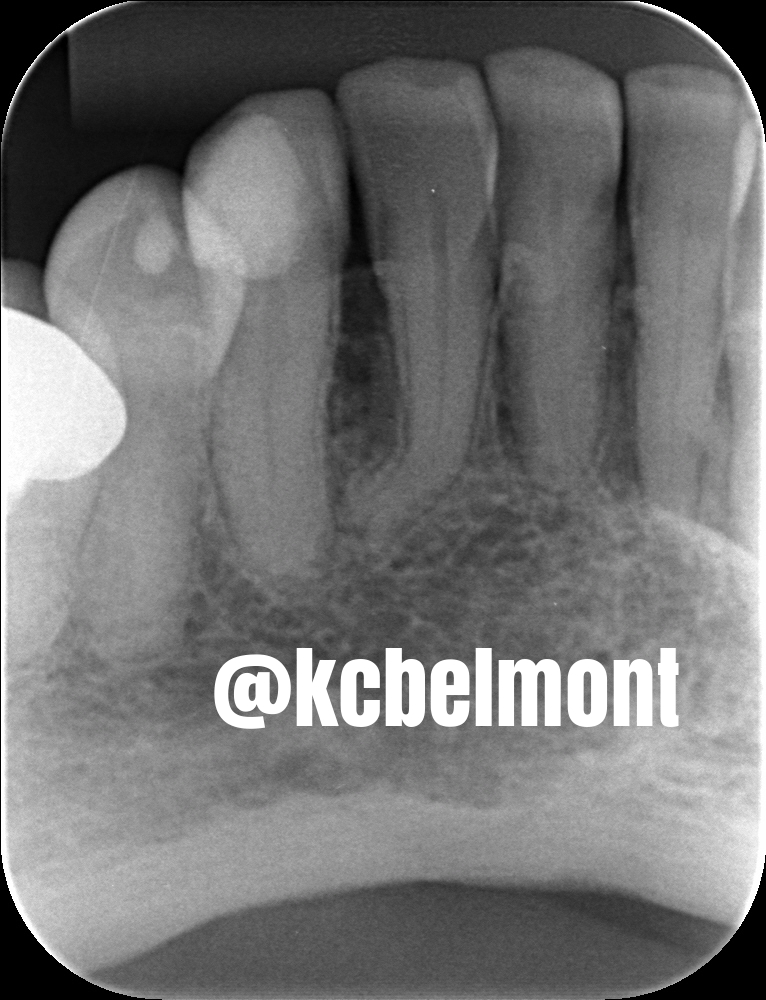

Dançando balé! Brincadeiras a parte....trata-se de uma dilaceração radicular, o que nada mais é que uma curvatura acentuada da raiz.

Nesta radiografia periapical, observamos dilaceração radicular no dente 42.